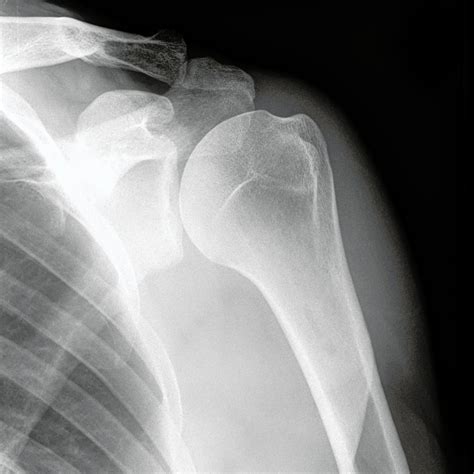

Interpreting a Shoulder X-Ray Normal Result

When a shoulder X-ray normal result is reported, it means that the X-ray images do not show any visible abnormalities in the bones or joints. This can be reassuring for patients experiencing shoulder pain, as it indicates that there are no obvious fractures or dislocations. However, it is important to note that a normal X-ray does not rule out all possible causes of shoulder pain.

• No Visible Fractures: The bones of the shoulder appear intact, with no signs of breaks or cracks.

• No Dislocations: The bones are properly aligned, indicating that there is no dislocation of the shoulder joint.

• No Arthritis: There are no visible signs of bone spurs, joint space narrowing, or other indicators of arthritis.